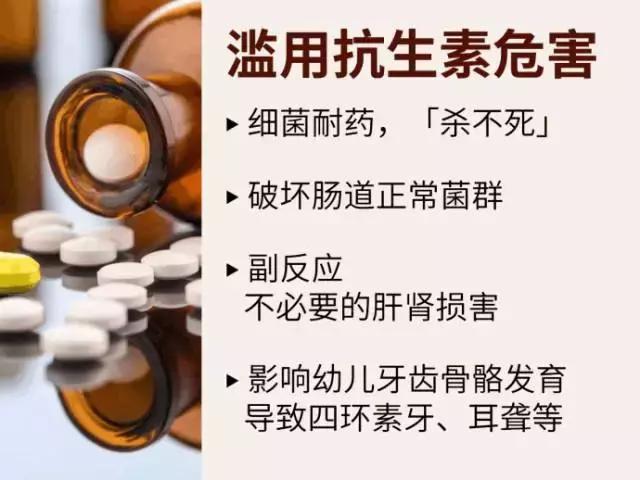

滥用抗生素的危害

用通俗的话来解释,假设人体内是一个场地,人体体内本身存在一些“和谐稳定”的菌落,一颗抗生素吞下来,不小心把这个菌落的A杀死一些,不小心把那个菌落的B又杀死一些,或者把某个菌落全灭,很容易导致这些菌落的“其他菌”不满顺势*反造**,产生一些斗争,可最终伤害的却是人体这个“战争场地”。

而当下次这颗抗生素再来捣乱时,这些菌落早就已经吸取前菌教训做好了防护措施,以至于抗生素无法再杀死这些菌落,导致抗生素失效。

滥用抗生素的危害,也不用我过多赘述了,只要大家记住,抗生素虽然很神奇,但并不是万能药,他的治疗效果也是有针对性的,在面对某些细菌感染时它会是个得力的伙伴,但在对抗其他强敌时,它便会毫无用武之地。请谨慎用药,对自己负责!